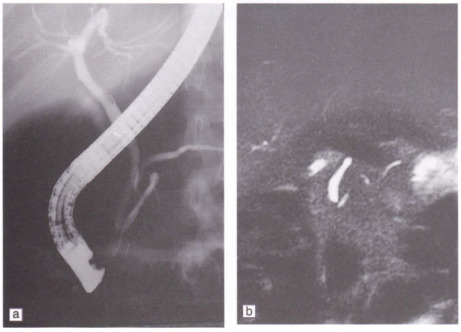

Nội soi mật tụy ngược dòng (ERCP)

Đó là Nội soi mật tụy ngược dòng (ERCP) lấy sỏi tránh phải thực hiện một ca mổ hở. Kỹ thuật này ngày càng được áp dụng rộng rãi cùng với các phương pháp truyền thống, nhất là ở bệnh nhân có tiền căn mổ bụng trước đó, lớn tuổi, có nhiều nguy cơ khi phẫu thuật hở.